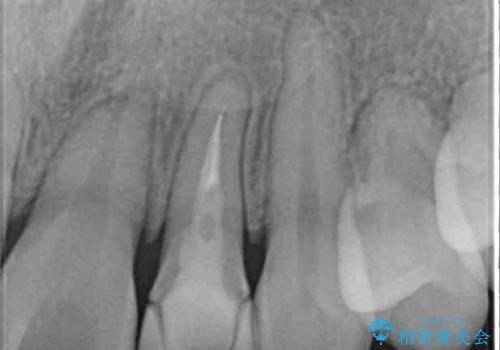

前歯には治療中の仮歯が装着されていたため、矯正治療後にオールセラミッククラウンにて補綴治療を行うこととしました。

抜歯矯正は2年から2年半程度の治療期間を要することが一般的ですが、僅か1年1ヶ月で終了しました。

あっという間に気になっていた歯並びが改善し、患者様には大変満足していただきました。